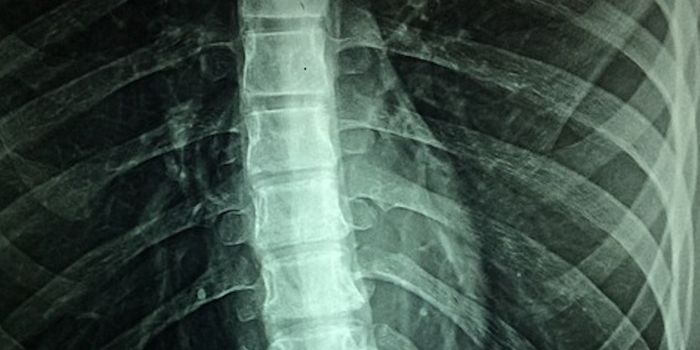

Read the latest articles about newly released neuroscience research and advances in experimental techniques. Topics include research news in neuroscience, neurology, psychology, brain science and cognitive sciences.